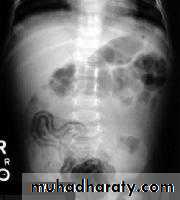

Diagnosis:-Complete blood count.-Blood culture.-Plain abdominal x-ray: initially shows separation of bowel loops due to ascitis& fluid levels. Periluminal tramlines indicating intramural gas [pneumatosis intestinalis]. Later signs include gas in the portal tree& gas under the diaphragm following perforation.The differential diagnosis of NEC includes sepsis withintestinal ileus or a volvulus. Both conditions can present with systemic signs of sepsis and abdominal distention.

Necrotizing enterocolitis, shows pneumatosis intestinalis